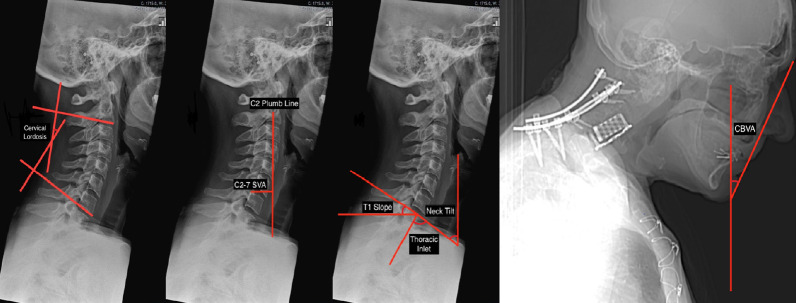

When assessing a CD, the following parameters should be measured using lateral radiographs in the neutral and extension position: CL, C2–7 sagittal vertical axis (C2–7 SVA), chinbrow vertical angle (CBVA), T1 slope (T1S), thoracic inlet angle (TIA), and neck tilt (Fig. 1).

Fig. 1.

Radiographic parameters for cervical alignment. SVA, sagittal vertical axis.

There are at least 4 established methods for measuring CL: the modified Cobb method (mCM), the Ishihara index, Harrison’s posterior tangent method, and Jackson physiological stress lines [3,5]. The mCM is the most common approach, wherein 2 lines are drawn along the C2 and C7 inferior endplates, after which 2 additional lines perpendicular to the original ones are drawn. The angle subtended by the perpendicular lines is the CL. In actuality, modern software will compute the angle directly based on the lines parallel to the endplates. It is conventional to use negative angles for lordosis and positive angles for kyphosis. Of note, one modification is to use the line connecting the anterior and posterior tubercles of C1 as the upper reference line. This can be helpful, because the average total CL in asymptomatic adults is thought to be approximately -40°, with nearly 80% of the lordosis coming from C1–2 [6]. Only 15% of the total CL, or roughly 6°, can be found at C4–7. Men and women do not differ in their total CL, but older adults are known to have increased CL as a compensatory mechanism for increasing thoracic kyphosis and decreasing LL [6,7].

The C2–7 SVA is a widely used measure of regional sagittal alignment, and has been associated with health-related quality of life (HRQoL) metrics [8]. It is computed by measuring the distance between a plumb line dropped from the centroid of C2 (the odontoid) and a vertical line drawn from the posterior edge of the superior endplate of C7. One of the few studies to measure the C2–7 SVA in asymptomatic adults, using upright EOS films, reported an average value of 21.3 mm [9]. Theoretically, values significantly greater than that should be a source of disability because energy must be expended on paraspinal and neck muscles to maintain horizontal gaze. However, high-level evidence of a relationship between disability and increased C2–7 SVA on neutral lateral radiographs has yet to emerge.

An indirect measure of horizontal gaze is the CBVA, which is obtained by computing the angle subtended by a vertical line and a line drawn from the chin to the eyebrow. CBVA can be measured using either upright EOS films that include the skull or using clinical photographs. The patient must be standing with the hips and knees in extension and the cervical spine in a neutral or fixed position. Of note, CBVA can be estimated using either the slope of the line of sight (anterior/inferior margin of the orbit to the external auditory meatus) or the slope of McGregor’s line (posterior edge of the hard palate to the most caudal point of the occipital curve) [10]. By convention, the CBVA is considered positive when the head is facing down and negative when the head is facing up. There are varying reports as to normative values of the CBVA - one study suggests a value of -1.7° based on a cohort of asymptomatic adults [9], while another study reported that values between -4.7° and 17.7° are associated with minimal disability [10]. Many experts caution against overcorrection of cervical kyphosis, because a slightly positive CBVA (flexion) is necessary for many activities of daily living such as walking and using the bathroom. Suk et al. [11] have shown that achieving a postoperative CBVA < -10° can prevent the appropriate gaze when walking down stairs. The CBVA has gained traction in recent years as a guiding metric for the surgical correction of CD, and a general postoperative goal of 10° has been reported [5].

The final 3 parameters—TIA, T1S, and neck tilt—are interrelated. TIA is the angle subtended by the line emanating from the center of the T1 endplate and perpendicular to the T1 endplate and a line connecting the center of the T1 endplate and the upper end of the sternum. It can be measured using lateral radiographs, computed tomography, or MRI. T1S is the angle subtended by a horizontal line and a line parallel to the T1 upper endplate, and neck tilt is the angle subtended by a vertical line and a line connecting the sternum to the center of the T1 upper endplate. These 3 parameters are analogous to pelvic parameters - neck tilt is akin to pelvic tilt (PT), T1S is akin to sacral slope (SS), and TIA is akin to PI. In fact, TIA=T1S+neck tilt, just as PI=SS+PT [3].

T1S is emerging as a uniquely important parameter for CD because it can help predict the ideal CL for a patient, just as PI can be used to determine the appropriate LL. Specifically, Staub et al. [12] have reported that CL=T1S–16.5°± 2°.